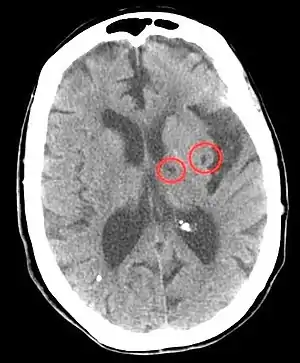

| CT scan of two lacunar strokes. | |

Lacunar stroke or lacunar cerebral infarct (LACI) is the most common type of ischemic stroke, resulting from the occlusion of small penetrating arteries that provide blood to the brain's deep structures. Patients who present with symptoms of a lacunar stroke, but who have not yet had diagnostic imaging performed, may be described as having lacunar stroke syndrome (LACS).

According to Koffler et al., lacunes are derived from an "occlusion of a single deep penetrating artery that arises directly from the constituents of the circle of Willis, cerebellar arteries, and basilar artery". Other lesions that are associated with lacunes appear in the "deep nuclei of the brain (37% putamen, 14% thalamus, and 10% caudate) as well as the pons (16%) or the posterior limb of the internal capsule (10%)". These lesions are less common within other brain regions such as the cerebellum, cerebral white matter and anterior limb of the internal capsule.[9]